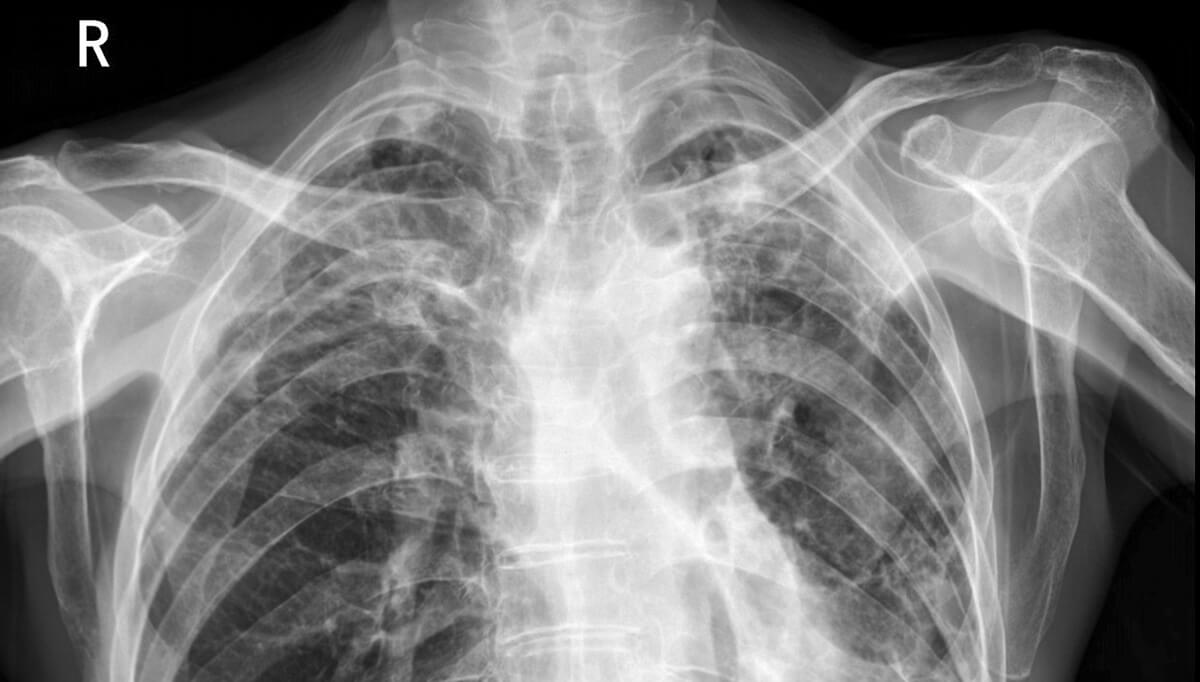

从技术参数来看,4K医疗显示器(分辨率3840×2160)的像素密度是传统2K显示器的4倍,能呈现更多影像细节。在放射科日常诊断中,肺部CT的微小结节、乳腺钼靶的细微钙化点,或是骨科X光片的骨小梁结构,这些易被低分辨率显示器忽略的细节,在4K屏幕上能清晰呈现。有临床数据显示,使用4K医疗显示器后,肺部微小结节检出率提升,有效降低漏诊风险——这是高分辨率最核心的诊断价值。